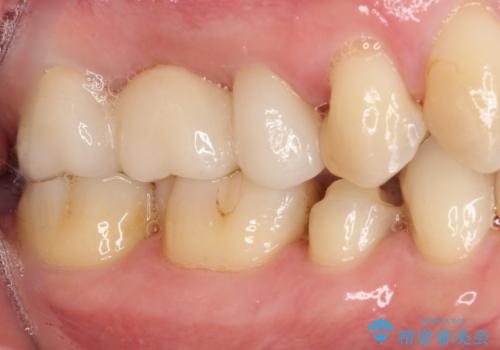

以前治療した詰め物が欠けた オールセラミッククラウンによる補綴

- 他院にて治療した詰め物が欠けてしまった事を主訴に来院された患者様です。

詰め物の範囲が大きく、部分的な詰め物では再び割れてしまうリスクが高いため、

オールセラミッククラウンにて補綴することとしました。

しみる症状はなくなり、見た目もきれいになり、とても満足されました。